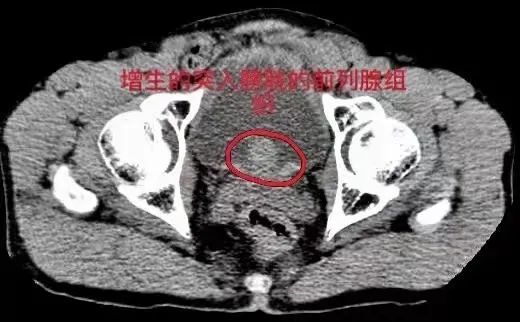

前列腺增生ct

为ct显示前列腺明显增大,向膀胱内明显突起 .

盆腔ct示:前列腺